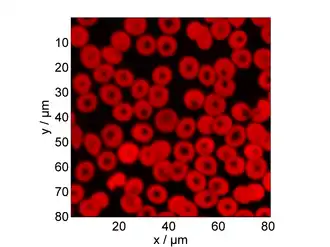

where is the optical wavelength and is the numerical aperture of the optical objective lens.[2] The lateral resolution of OR-PAM can be improved by using a shorter laser pulse and tighter focusing of the laser spot. OR-PAM systems can typically achieve a lateral resolution of 0.2 to 10 μm, allowing OR-PAM to be classified as a super-resolution imaging method.

Visible light absorbers (λ = 400 to 700 nm) include oxyhemoglobin, deoxyhemoglobin, melanin, and cytochrome c. Visible light photoacoustic microscopy is particularly useful in determining hemoglobin concentration and oxygen saturation due to the difference in absorption profiles of oxyhemoglobin and deoxyhemoglobin. Real-time analysis can then be used to determine blood flow speed and oxygen metabolism rate.[3] In addition, photoacoustic microscopy is capable of early melanoma detection due to the high concentration of melanin found in skin cancer cells.